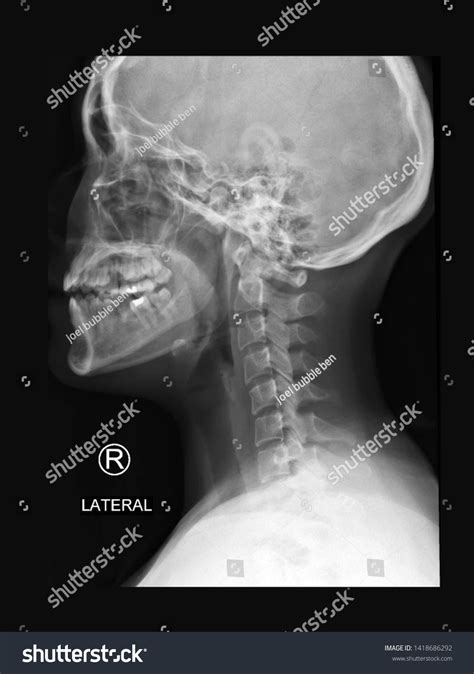

A Normal Neck X Ray is a radiographic imaging technique used to visualize the bones, joints, and soft tissues of the neck. It is a non-invasive procedure that helps in diagnosing a wide range of conditions, including fractures, dislocations, arthritis, and infections. The term “normal” in this context refers to the expected appearance of the neck structures in the absence of any pathological conditions.

Interpreting a Normal Neck X Ray involves examining the images for any abnormalities. Key structures to assess include:

• Vertebrae: The seven cervical vertebrae (C1-C7) should be clearly visible and aligned.

• Intervertebral Discs: The spaces between the vertebrae should be uniform and without narrowing.

• Joints: The facet joints should be well-defined and without signs of degeneration or inflammation.

• Soft Tissues: The soft tissues, including muscles and ligaments, should appear normal without any swelling or masses.

• normal neck x ray images

• normal neck x ray female